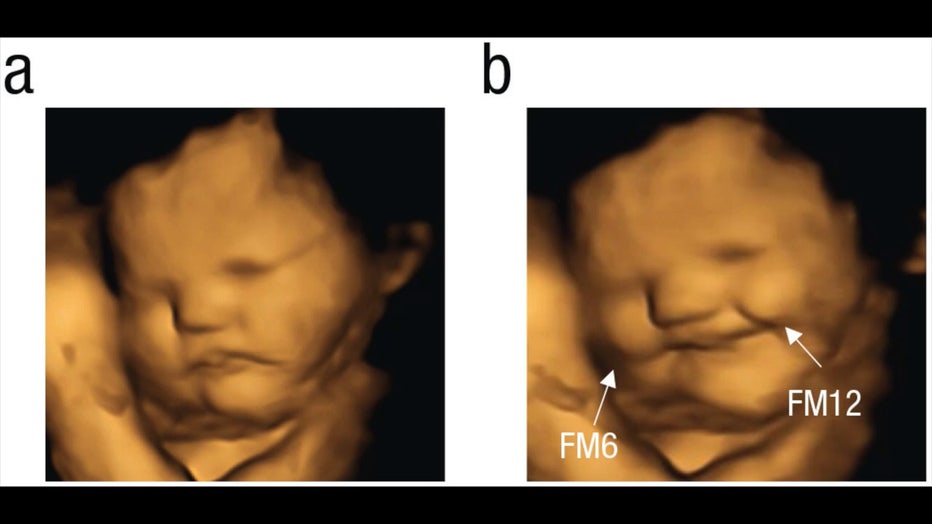

Fetus-kale.jpg

4D ultrasound scan showing before and after result after pregnant woman ingests kale capsule. (Beyza Ustun, Nadja Reissland, Judith Covey, Benoist Schaal, and Jacqueline Blissett via Storyful)

After a pregnant woman ingested either the kale or carrot capsule, it took about 30 minutes to see results, according to Blissett.

Each participant in the study would wait about 20 minutes after swallowing a capsule before they were given an ultrasound.

The fetuses exposed to the carrot capsule showed a more "laughter-face" expression, and the ones exposed to the kale capsules showed a more "crying-face" expression, according to researchers.